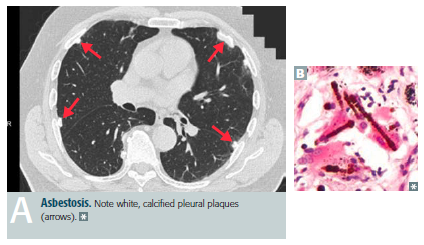

Asbestosis